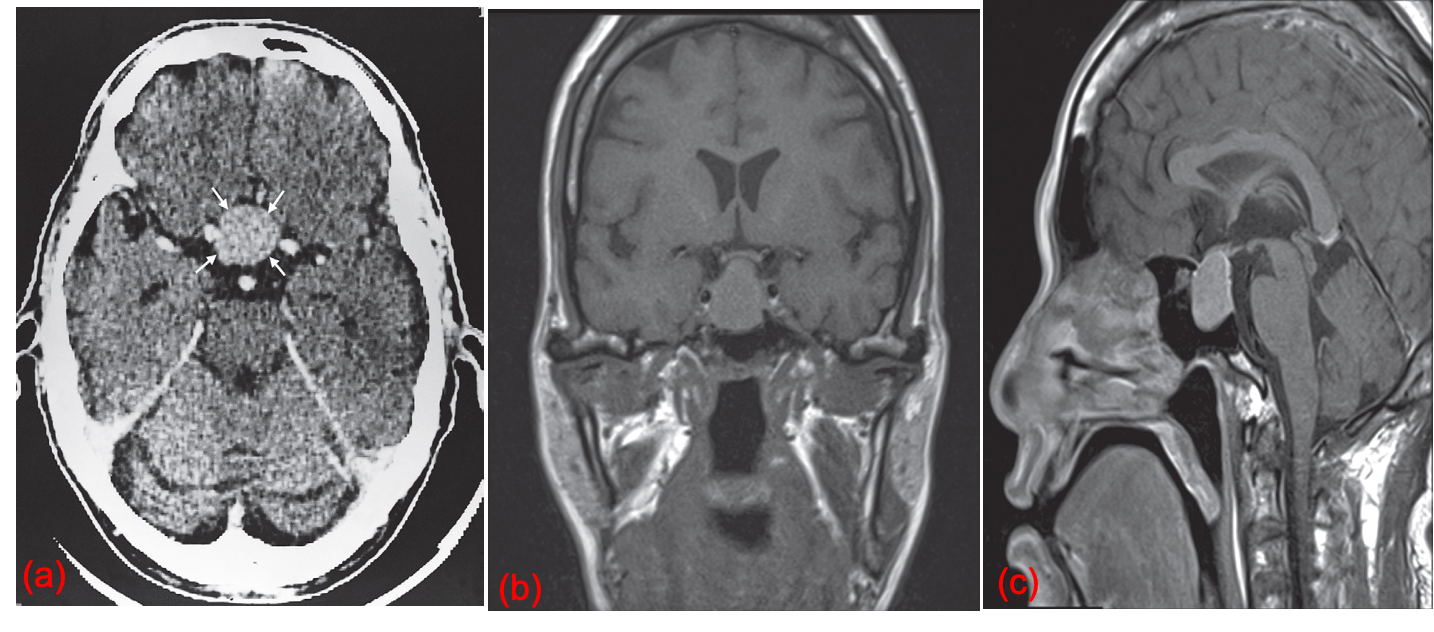

Pituitary tumor. (a) CT scan after contrast showing a mass in the pituitary fossa which enhances vividly (small arrows). (b) Coronal T1 MRI and (c) Sagittal T1 post contrast MRI showing a macroadenoma expanding the pituitary fossa and extending superiorly to touch the optic chiasm in the suprasellar cistern.